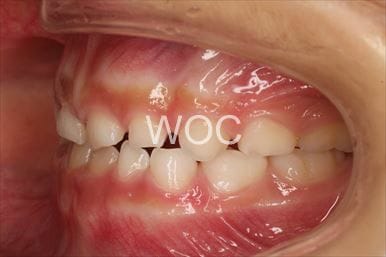

八重歯・叢生上のみ舌側矯正、下はエッジワイズ装置

上は舌側矯正を希望。ガタガタ(叢生)が強い。上顎右側中切歯・側切歯が歯科治療で連結してあったがそれを除去してから治療開始しました。

- 年齢:23歳女性

- 主訴:上下前歯のガタガタが気になる

- 基本矯正料金:103万円

- 治療期間:2年2ヶ月

- 非抜歯